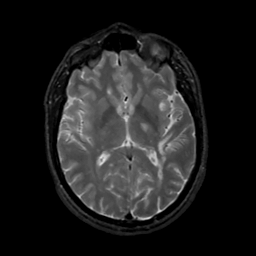

MR Study #4, March 3, 1991 -- Slice #26

[Home][Help][Clinical][Tour 1][Tour 2] Slice 26